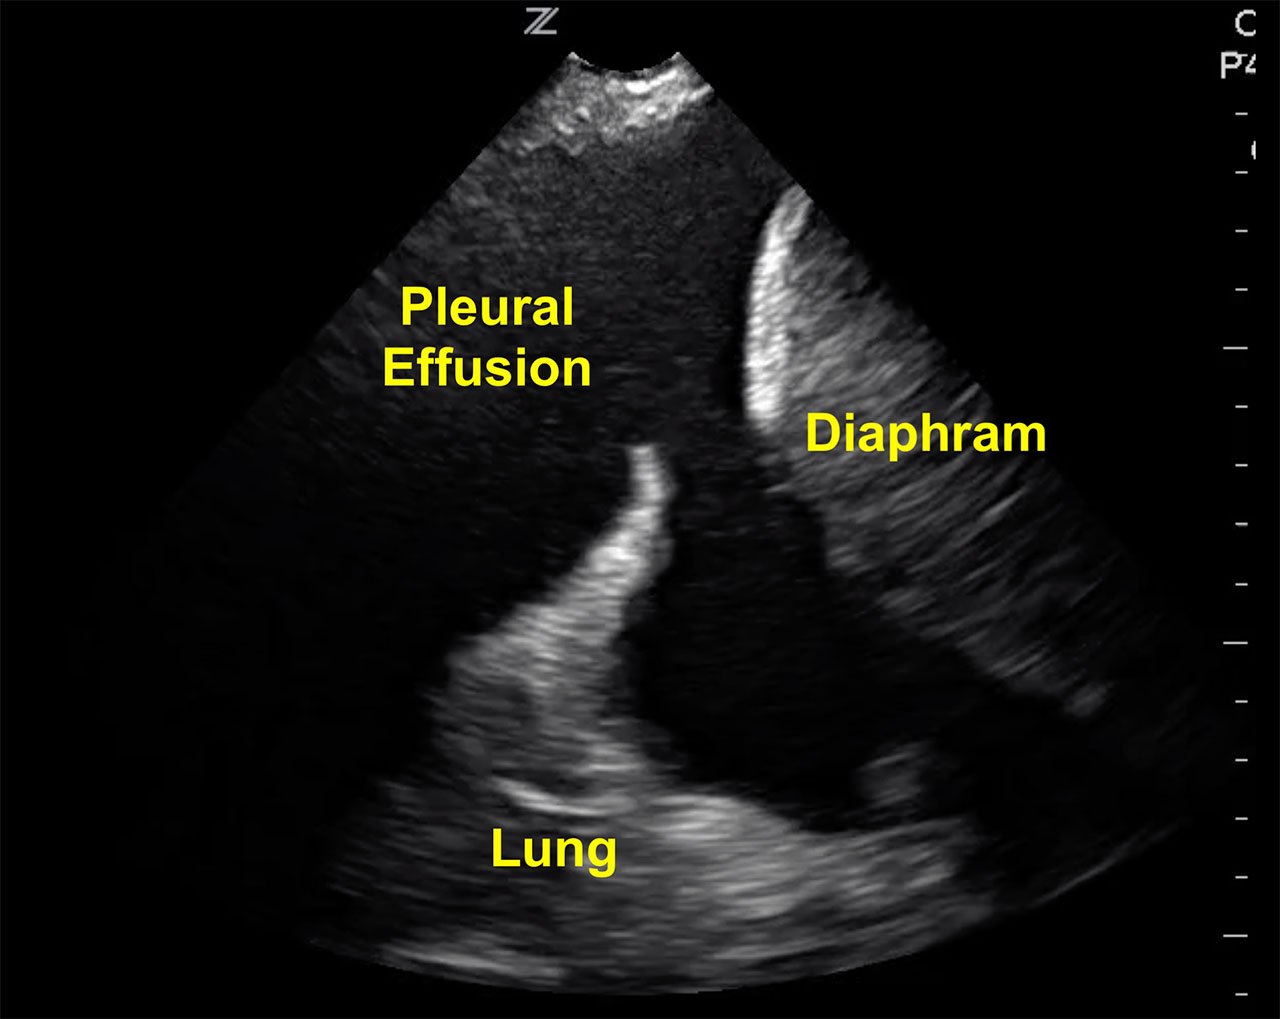

- Fluid in the pleural space appears anechoic and is readily detected above the brightly echogenic diaphragm when the patient is in a supine position

- Figure 1. Visualizing a large pleural effusion, diaphragm and liver

- Video 1. Large pleural effusion